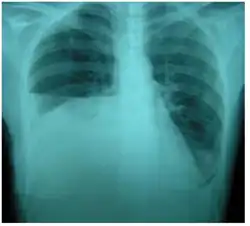

Chest X-ray showing urinothorax disappearing after treatment

Treatment mainly consists of treating the underlying disorder of the genitourinary tract.[2] It requires a multidisciplinary team that includes a pulmonologist and urologist. A nephrostomy tube or Foley catheter can be used to relieve any underlying obstruction. Any injuries are repaired.[11] When the underlying disorder is addressed, the urinothorax rapidly resolves. Thoracic surgery is usually not needed,[4] especially if respiratory symptoms are minimal or nonexistent.[2] Pleurodesis is also ineffective.[11] A chest tube can be used to drain urine from the pleural cavity.[12]